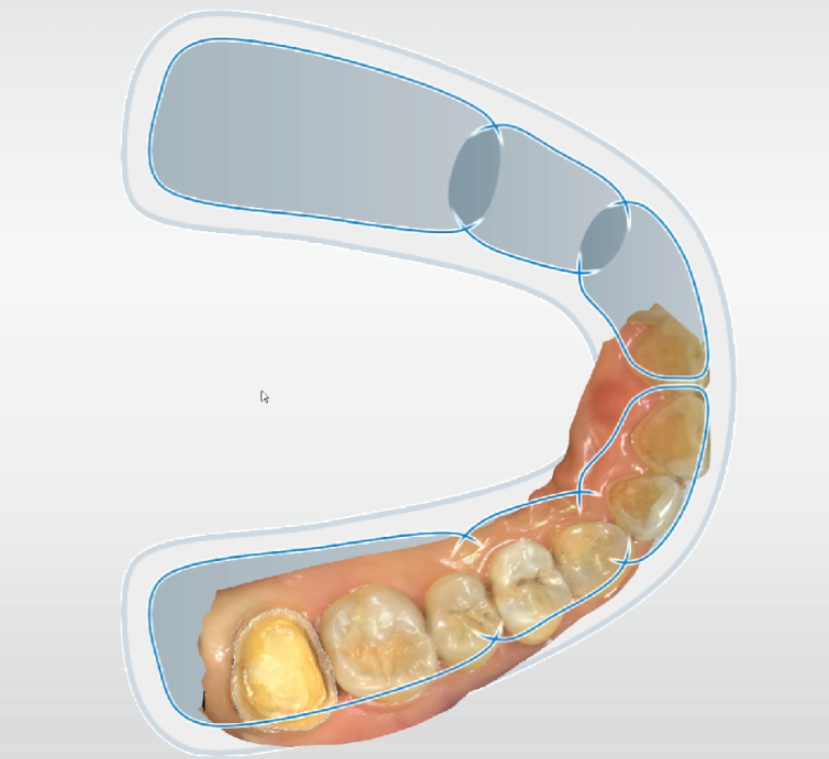

根管治疗后的牙冠修复是避免牙齿折断、延长使用寿命的关键步骤。根据牙齿位置和需求选择合适材料,并严格维护,可确保修复效果长期稳定。越早保护,越省成本!

所以,为了避免这种风险的出现,医生通常会在根管治疗修复后,为患者做一个新的牙冠或者高嵌体将牙齿保护起来。

行动建议:完成根管治疗后1个月内预约修复,避免延误!